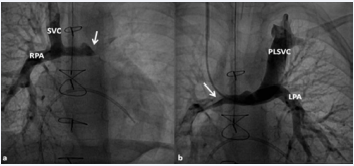

Figure 27 Selected cine frames in postero–anterior (a) and sitting up (b) views, demonstrating bidirectional Glenn procedure (the superior vena cava [SVC] is anastomosed with the right pulmonary artery [RPA]) in two different patients during Stage II of Fontan procedure. Unobstructed flow from the SVC to the right (RPA) and left (LPA) pulmonary arteries is shown [82].

Figure 27: Selected cine frames in postero–anterior (a) and sitting up (b) views, demonstrating bidirectional Glenn procedure (the superior vena cava [SVC] is anastomosed with the right pulmonary artery [RPA]) in two different patients during Stage II of Fontan procedure. Unobstructed flow from the SVC to the right (RPA) and left (LPA) pulmonary arteries is shown [82].Figure 28 Selected cineangiographic frames showing a bilateral bidirectional Glenn procedure (Stage II). In a, an injection into the superior vena cava (SVC) shows prompt opacification of the right pulmonary artery (RPA). The arrow in a points to the unopacified blood from a persistent left superior vena cava (PLSVC). In b, an injection into the PLSVC shows prompt opacification of the left pulmonary artery (LPA). The arrow in b points to the unopacified blood from the right SVC. Note the unobstructed flow from the respective SVCs into the pulmonary arteries [82].

Figure 28: Selected cineangiographic frames showing a bilateral bidirectional Glenn procedure (Stage II). In a, an injection into the superior vena cava (SVC) shows prompt opacification of the right pulmonary artery (RPA). The arrow in a points to the unopacified blood from a persistent left superior vena cava (PLSVC). In b, an injection into the PLSVC shows prompt opacification of the left pulmonary artery (LPA). The arrow in b points to the unopacified blood from the right SVC. Note the unobstructed flow from the respective SVCs into the pulmonary arteries [82].

Stage II - Bidirectional Glenn. Irrespective of the type of palliative intervention during the neonatal period, bidirectional Glenn procedure [41], i.e., anastomosis of the SVC to the right PA, end-to-side is performed at an approximate age of 6 months. If a prior BT shunt is present, it is ligated at the same time. While performing the procedure at 6 months is generally accepted, the Glenn can be performed as early as 3 months provided normalcy of PA pressure and anatomy can be documented. In babies with persistent left SVC, bilateral bidirectional Glenn is performed especially in patients with a small or absent left innominate vein. A bidirectional Glenn procedure may also be performed for patients with infra-hepatic interruption of the inferior vena cava (IVC) with azygos or hemiazygos continuation, and such a procedure is called a Kawashima procedure by some surgeons.

Echocardiographic and angiographic examples of the bidirectional Glenn procedure are shown in Figures 25-28.